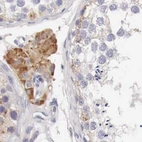

Immunohistochemistry analysis in human epididymis and lymph node tissues using Anti-NSDHL antibody. Corresponding NSDHL RNA-seq data are presented for the same tissues.